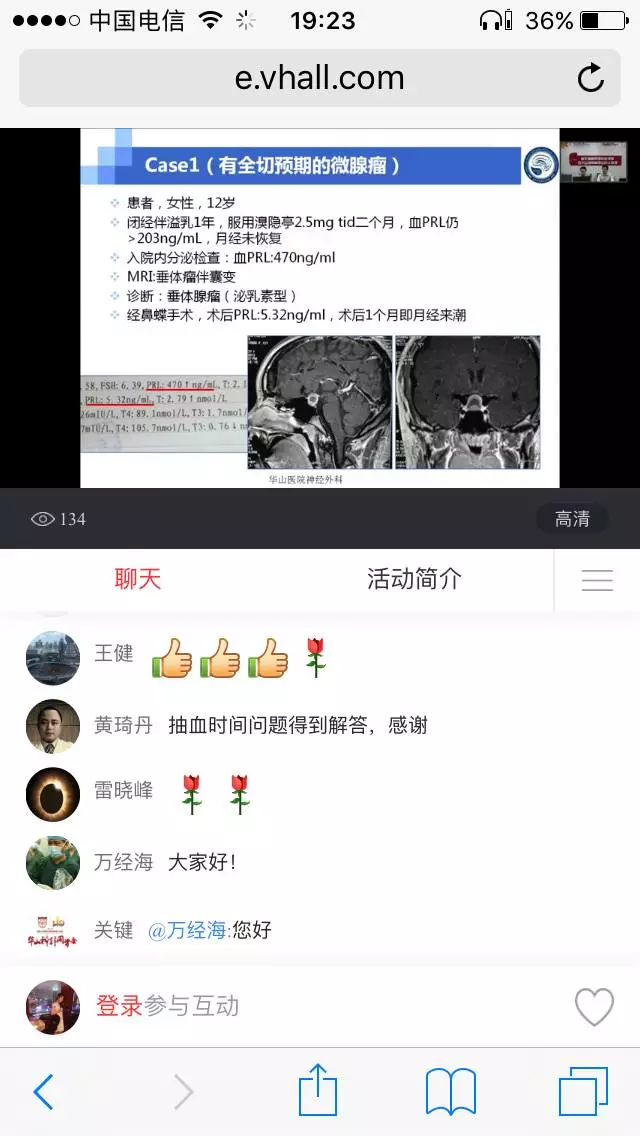

对于生育期垂体微腺瘤如何处理,能否怀孕期间服用溴隐停?

请问一公分的有出血囊变的泌乳素瘤术后了恢复到17,假包膜可能有一点点残留,怀孕生育哺乳泌乳素自然的升高会不会刺激泌乳素瘤复发?

临床上有时遇到闭经患者,泌乳素升高2-4倍,垂体磁共振阴性,临床如何处理合适?